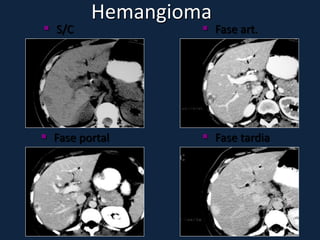

Hemangioma

►Tumor hepático benigno mais comum (5-20% pop.).

►♀ > ♂, no período pós-menopáusico.

►Estruturalmente, consistem de canais vasculares

interconectados em meio a estroma fibroblástico.

São alimentados por ramos da artéria hepática, e sua

circulação interna é lenta.

►Pode ser do tipo capilar ou do tipo cavernoso.

►Assintomáticos.

►Geralmente solitário, de localização subcapsular e

em regiões posteriores do lobo direito.

► s/c: Lesões bem definidas, lobuladas, hipodensas ao parênquima e

isodensas aos vasos intra-hepáticos.

► c/c: (aspecto típico em lesões 2-10cm):

 Fase arterial: Realce periférico nodular e descontínuo, com áreas

nodulares ou globuliforme, da periferia para o centro da lesão. Centrípeto.

 Fase portal: Realce progressivo e centrípeto (da periferia para o centro).

 Fase tardia: Ocorre o preenchimento completo e homogêneo da lesão, com

realce persistente.

► Tempo de enchimento completo depende do tamanho da lesão

► Lesões pequenas (<2cm): enchimento completo rápido

► Lesões grandes (>10cm): preenchimento incompleto da lesão (presença

de trombos, áreas de fibrose e/ou necrose).

 Fase art.      Fase portal    Fase tardia

 S/C              Fase art.

 Fase portal      Fase tardia